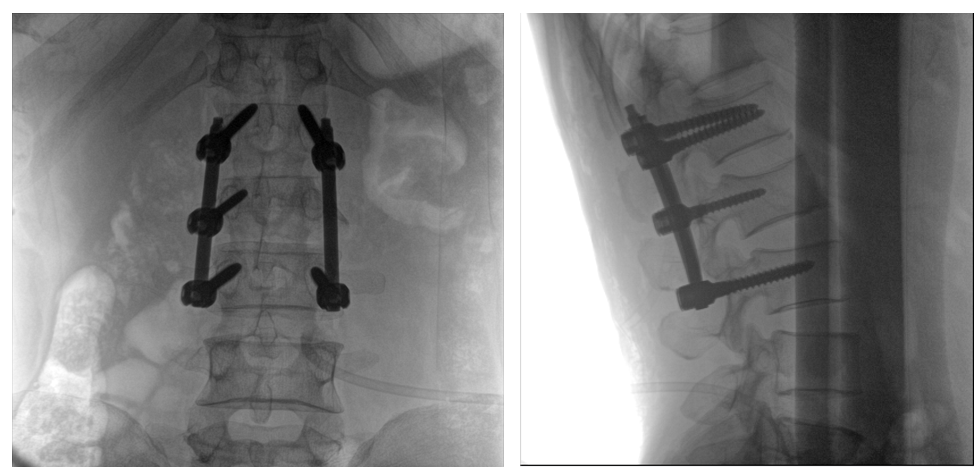

普愛醫(yī)療PLX119C大平板一體式C形臂采用30CM×30CM的平板探測器,在脊柱和長骨骨折等骨科手術治療中,獲取更大視野、更清晰的骨折部位圖像,能夠有助于醫(yī)生在術中及時了解和評估骨折部位的對位、對線情況,且能進行長度和角度測量,為進一步提高手術質(zhì)量提供強有力的支持。